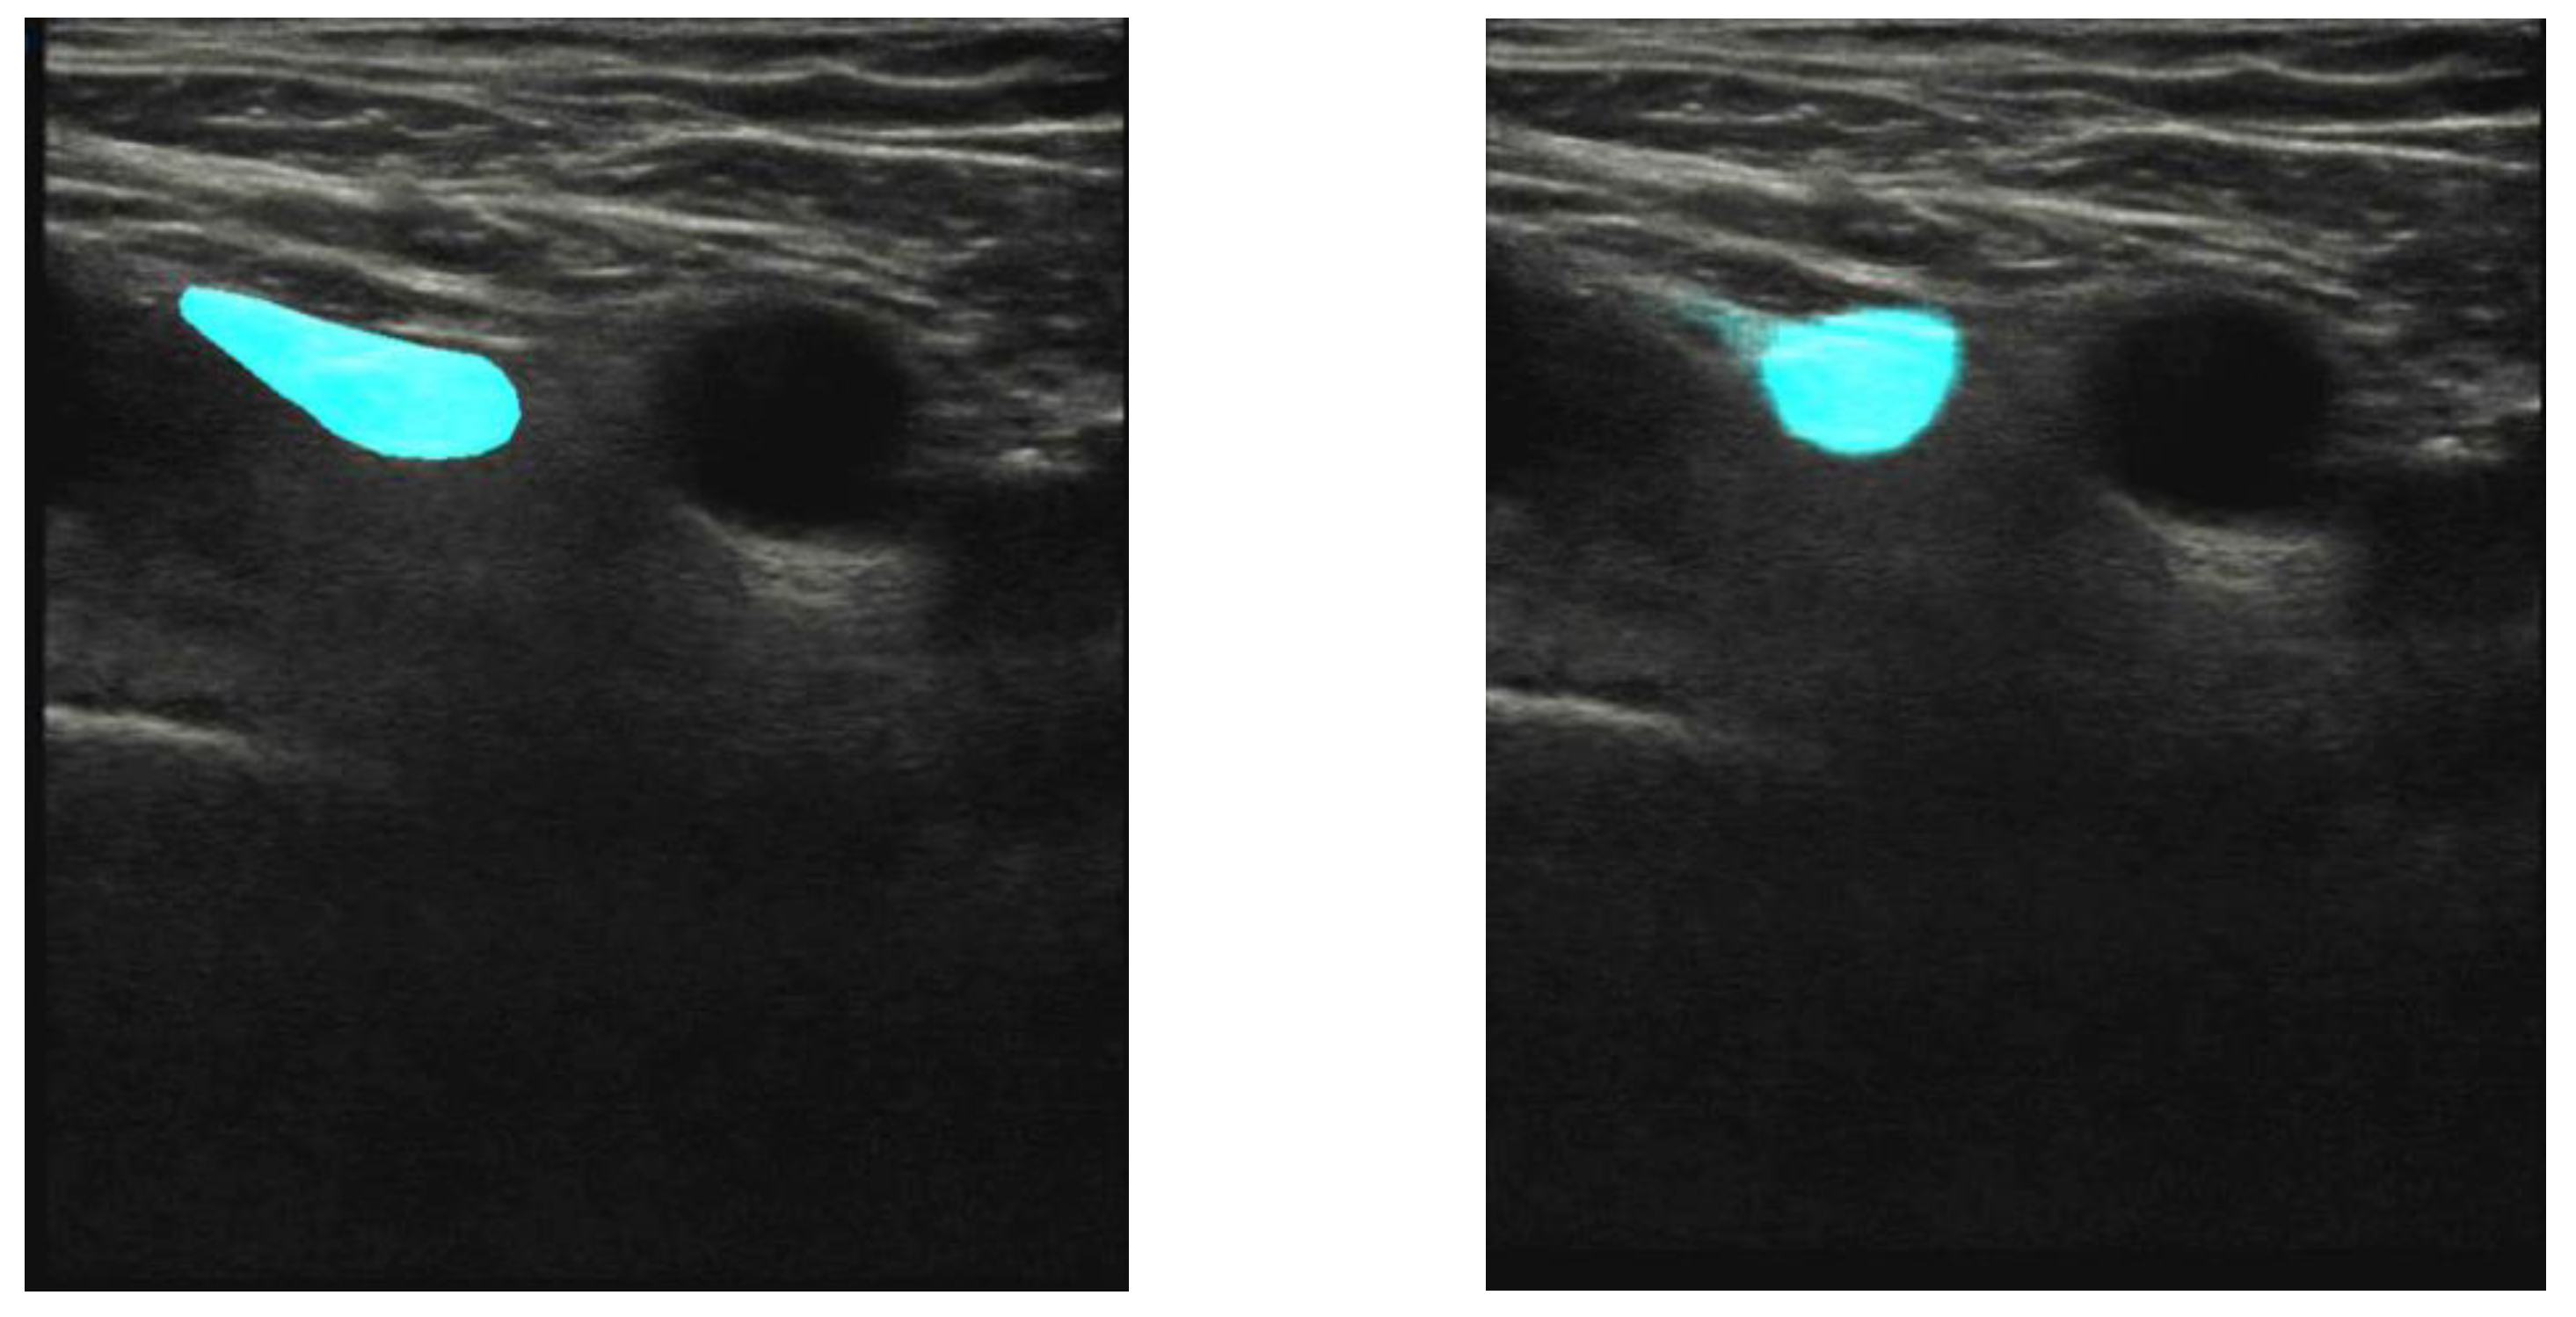

Figure 4.

Test image of a participant’s right groin, the same as used in Figure 1. The femoral artery is seen as a black circular area in the center of the image. Left panel: expert’s manual annotation of the femoral nerve (cyan). Right panel: trained U-net segmentation of the femoral nerve. The overlap between the annotated and segmented areas, described as IoU, is 57% in this case.